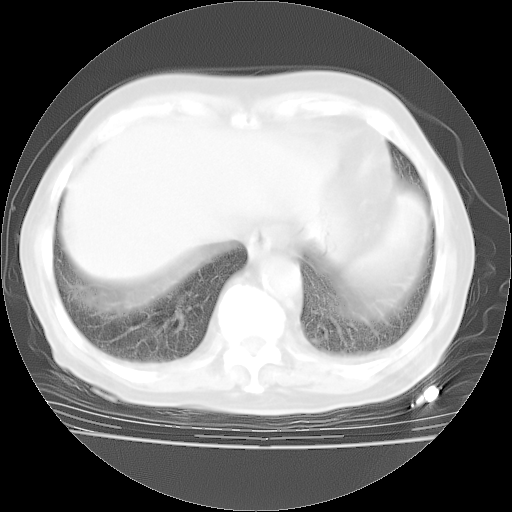

4月28日肺部CT——再次出现类似去年5月9日——透光度降低,“间质性”改变。

4月28日肺部CT——再次出现类似去年5月9日——磨玻璃样、间有“粟粒样”改变。